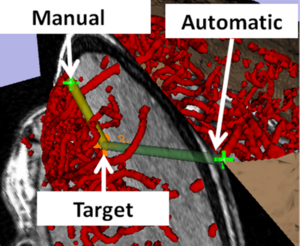

- 4.16 Compact Robotically Steerable Image-Guided Instrument for Multi-Adjacent-Point (MAP) Targeting